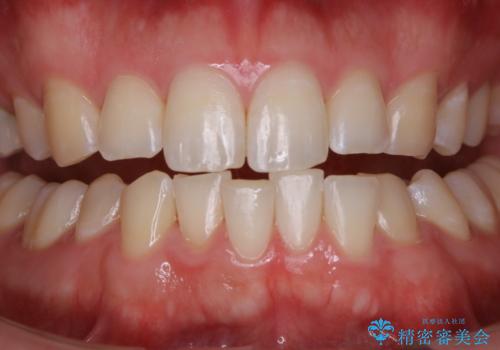

コーヒーの着色落としをPMTCでキレイに

普段の飲食物・歯磨き・生活習慣などにより着色の付き具合には個人差があります。どれくらいの頻度で行うことがベストかは、その都度担当の歯科衛生士とご相談します。

- 歯を白くする目的の施術ではありません